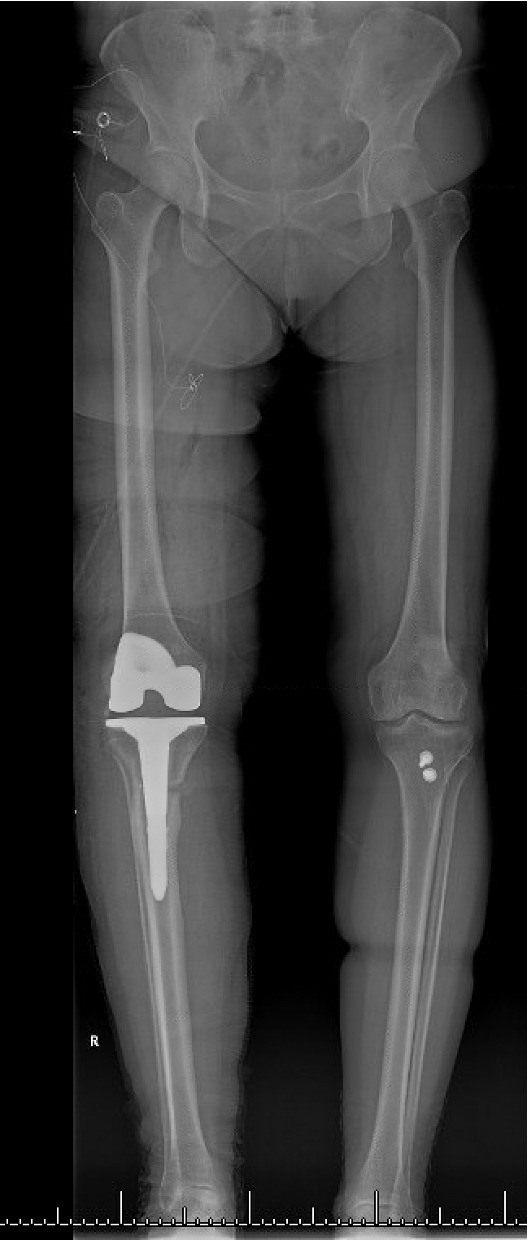

The total estimated blood loss was 300 mL, and no transfusion was required. The patient tolerated oral intake on the evening of surgery, completed her first physiotherapy session the following morning, and ambulated fifty feet with a rolling walker while wearing the hinged knee brace locked in extension. Following ambulation, full length lower extremity films were re-obtained, demonstrating neutral mechanical hip–knee–ankle axis (Figure 5). She was discharged home on post-operative day two with acceptable pain control and an incision that was clean, dry, and intact.

Quantitative range-of-motion and outcome-score data are summarized in Table 1. At the two-week clinic visit the incision was fully healed and sutures were removed. The patient continued full weight bearing in the brace. By six weeks the osteotomy displayed bridging callus across the osteotomy site (Figure 6), the brace was discontinued, and she achieved an unrestricted gait pattern without assistive devices. Four months after surgery, the patient had resumed activities such as tennis and reported no pain or swelling. Radiographs at that time demonstrated complete cortical union without any interval changes in alignment (Figure 7). At the nine-month assessment she reported hiking up to five miles and skiing on groomed slopes without limitation. Imaging showed continued consolidation of the osteotomy and stable components (Figure 8).